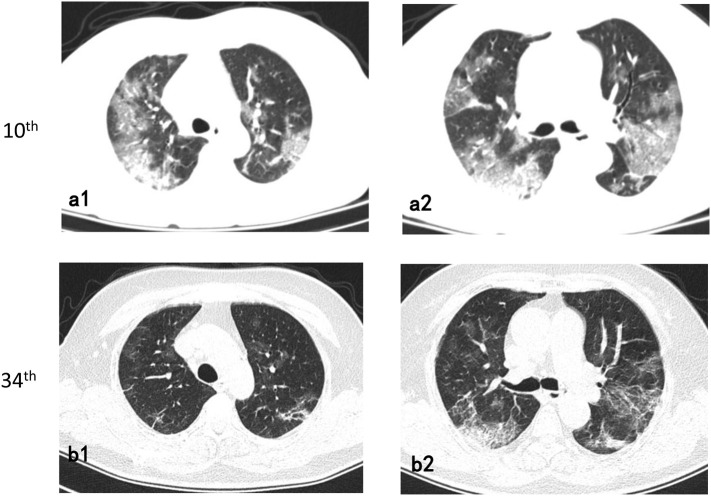

Fig. 1.

72-year-old/Female.

Follow-up axial chest CT images (34th day from onset) (b1-b2) showed a decrease in the extent of ground-glass opacities than the 10th day CT images and an increase in fibrotic lesions (a1-a2).